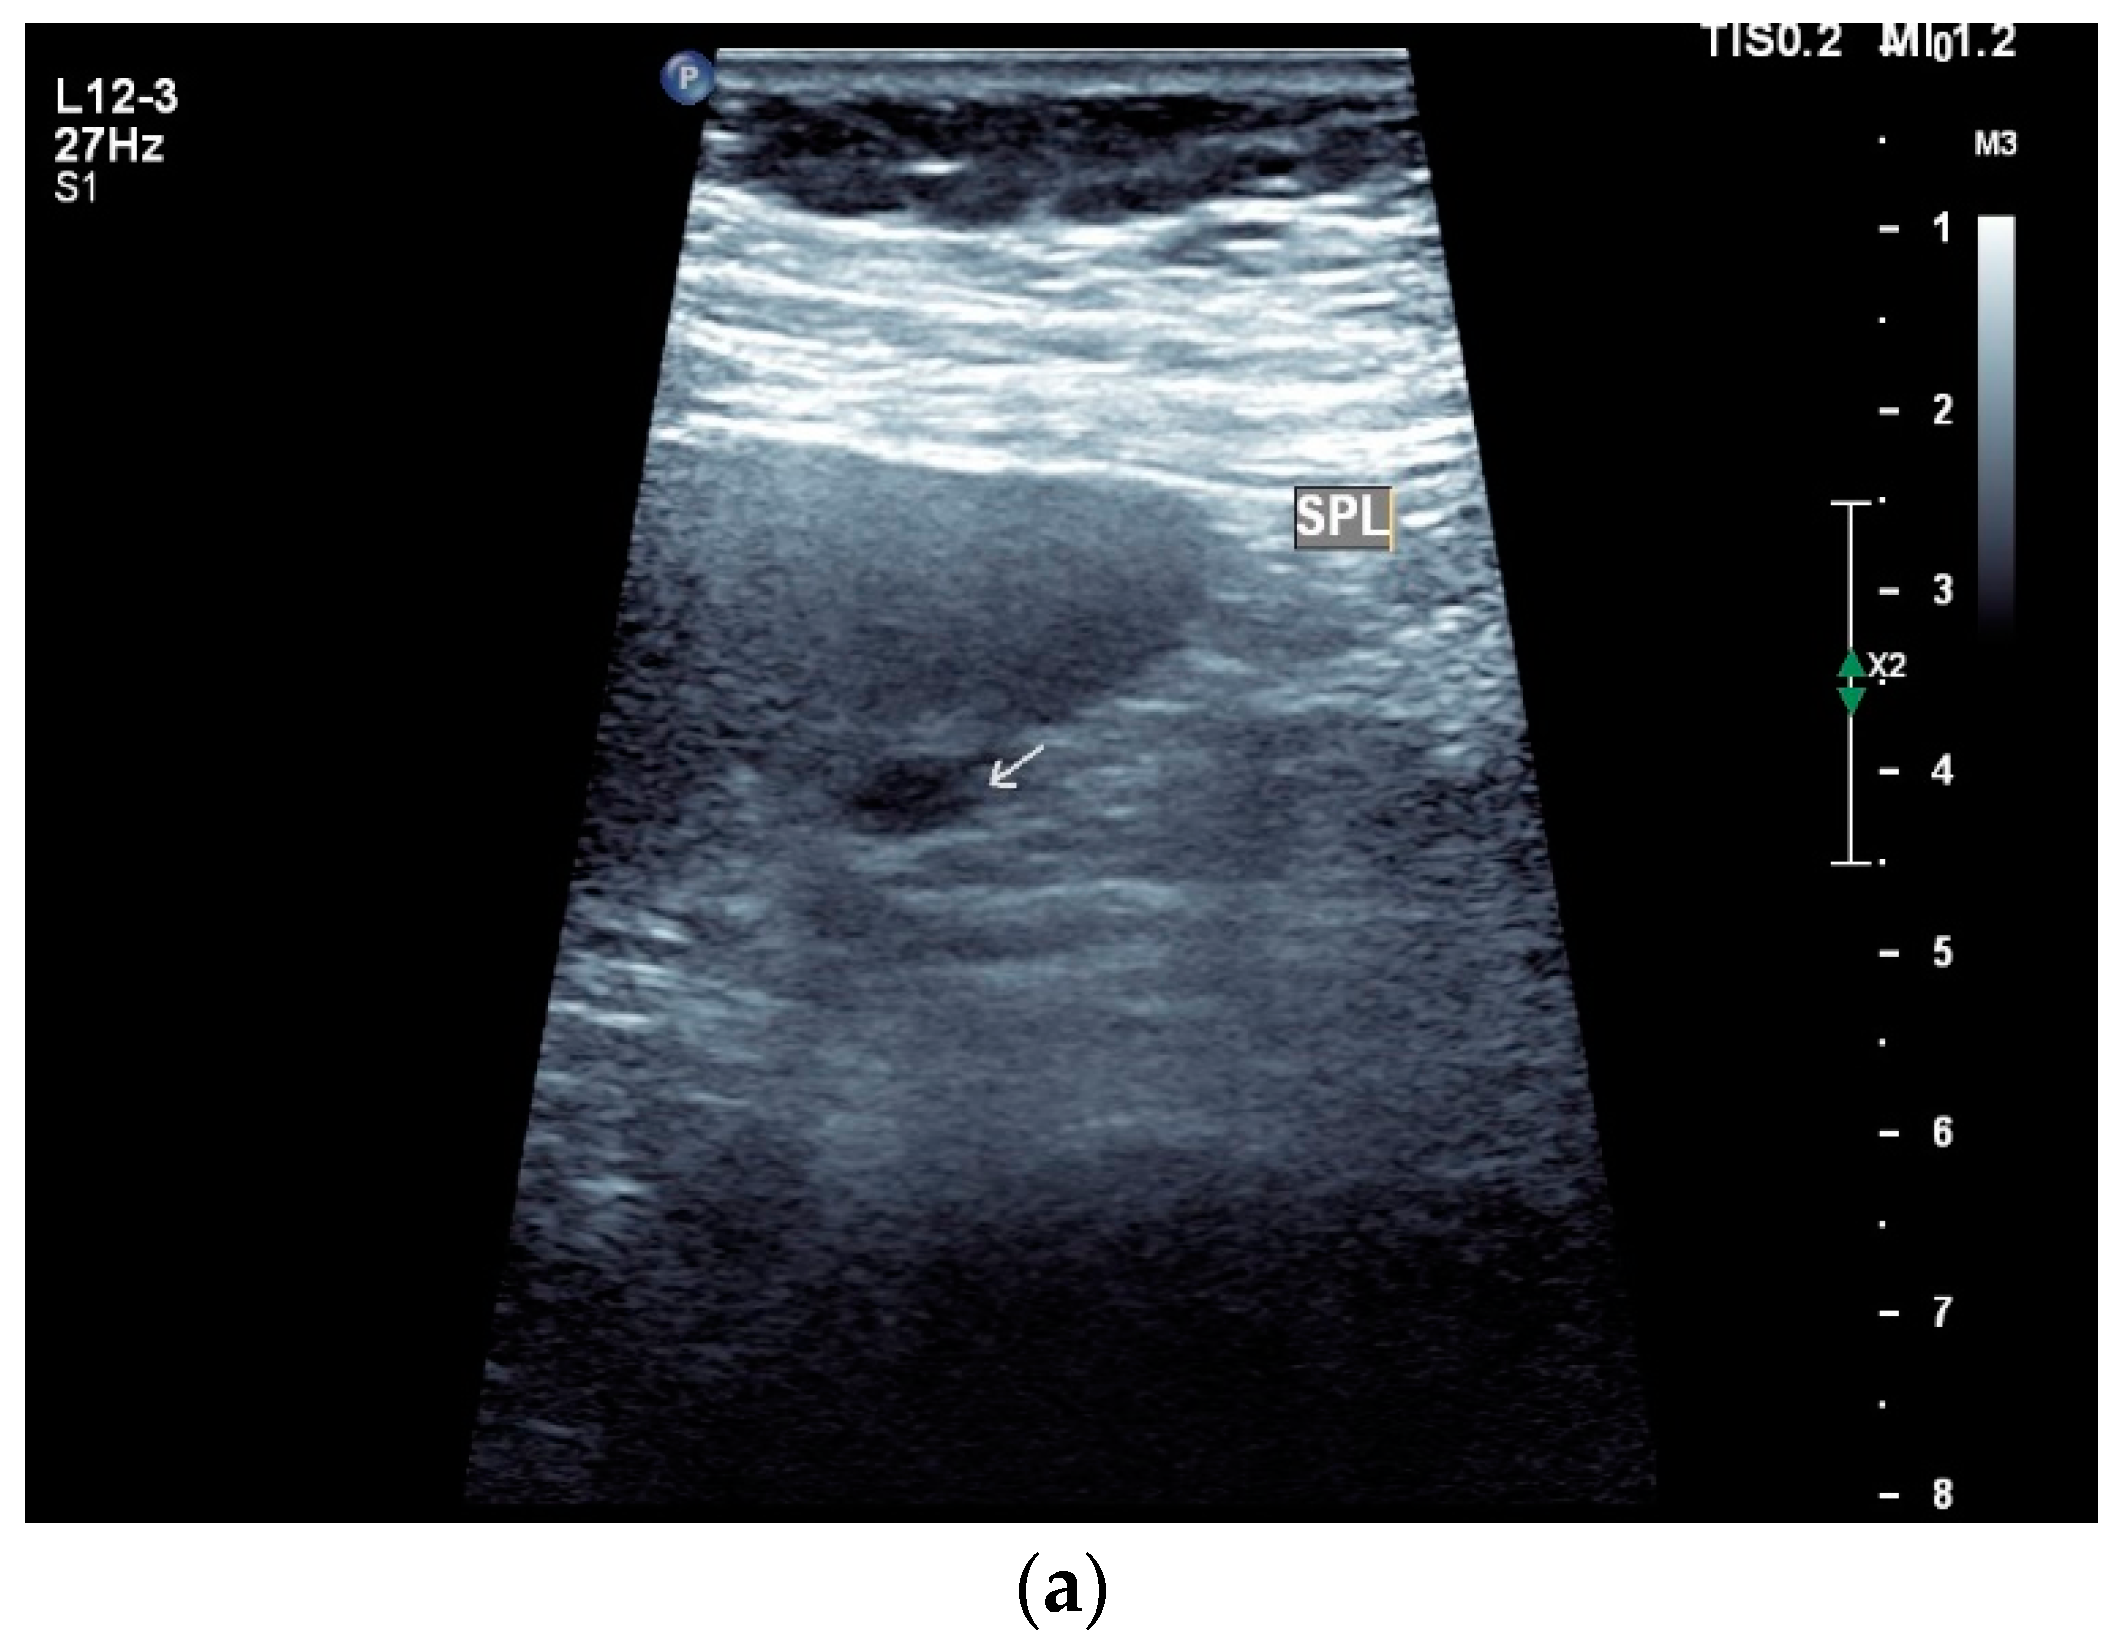

9. Spleen

Spleen involvement usually only occurs in disseminated disease. The manifestations are splenomegaly, hypoechoic micronodular (miliary), or macronodular lesions [8,74], as well as splenic abscesses [75] [Figure 4a–d]. In a group of patients with tuberculosis and mostly advanced HIV infection, 37% had splenic lesions [5]. In 33%, splenic lesions were associated with lymphadenopathy, and 16% each had splenic lesions and ascites or splenic lesions, ascites, and lymphadenopathy. Micronodular lesions may be indistinguishable. If this is suspected, examination with a high-resolution linear transducer is recommended. Using CEUS, splenic lesions in the arterial phase showed a hyperenhancement, followed by either a slow washout or a persistent enhancement in the middle and late parenchymal phase [76]. A fast washout was the exception, but nevertheless was also possible. These exceptional cases would therefore be difficult to differentiate from malignancies. There was also rim-like enhancement with central nonenhancement, like abscesses and septation-like enhancement [76]. Another study using CEUS in splenic manifestations of tuberculosis presented homogeneous enhancement (6.7%), heterogeneous enhancement (63.3%), and nonenhancement (30.0%). Most of the cases showed low enhancement. Among these cases, heterogeneous enhancement was divided into septal enhancement type (21.1%) and marginal enhancement type (78.9%) [77] [Figure 4c–g]. The most important differential diagnoses are non-Hodgkin’s lymphoma and other granulomatous inflammations, such as sarcoidosis, especially in the presence of lymphadenopathy. The splenic lesions must be differentiated from mycotic abscesses, leukemic infiltrates, and metastases. In the meta-analysis conducted by van Hoving et al. [78], splenic lesions as manifestations of abdominal tuberculosis had a broad sensitivity of 13–62% in five studies using B-mode ultrasonography. The specificity was higher, at 86–100%.

Figure 4.

Sonographic and CEUS features of splenic tuberculosis. Sonographic and CEUS features of splenic tuberculosis. Subcapsular splenic lesion (arrow) (a), subcapsular splenic lesion using a linear transducer of 12 MHz (arrows) (b). Histologically confirmed tuberculosis from mediastinal lymph nodes. Multiple small splenic lesions (c). Using CEUS with a linear transducer (9 MHz), these are slightly hypoenhanced in the arterial phase (d), and show a progressive washout in the course of the venous phase (arrows) (e). Subcapsular splenic lesion (arrow) with nonenhanced and hypoenhanced parts and hyperenhanced rims indicate a caseous necrosis (f). In another section, an interrupted spleen capsule (arrow) due to a rupture of the caseous necrosis can be assumed (g).